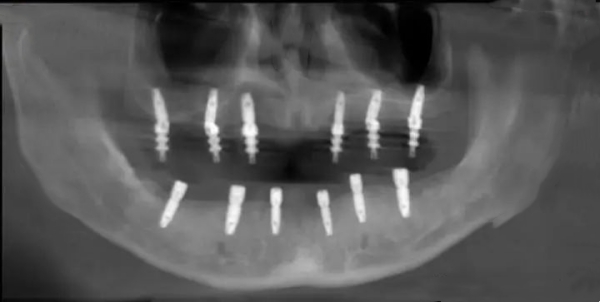

采用韩国进口种植体系统,配备数字化导板设计

核心优势:石门县少数拥有数字化种植中心的机构,正畸病例累计超500例。

种植科蒋辉医生具有10年临床经验,主攻即刻负重种植

设备配置:引进德国卡瓦CBCT、意大利灭菌系统,种植手术室达洁净标准。www.5#@9w.net

追求品质:康贝口腔(德国种植体 + 数字化导板)

复杂病例:澧阳口腔(骨增量技术成熟)